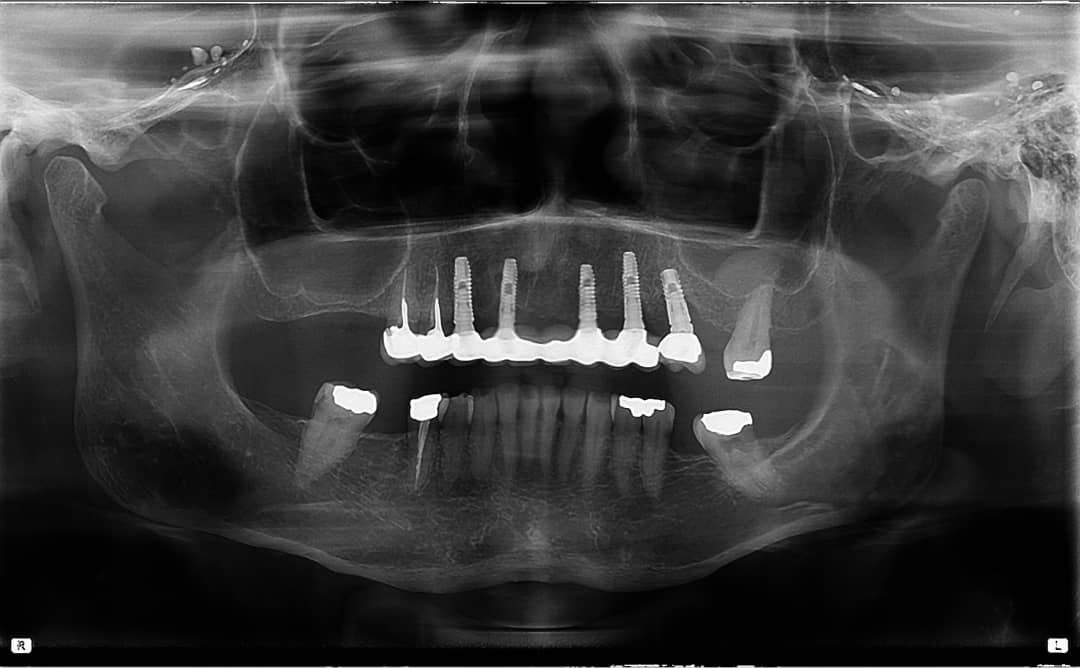

9. What option can be selected regarding the implants seen in this X ray?